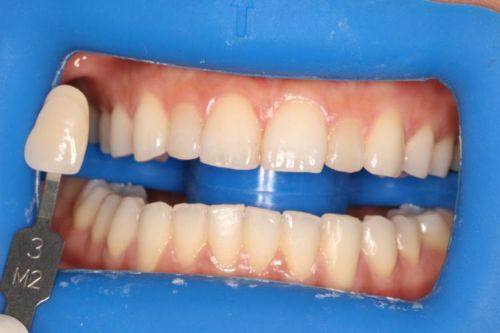

2. 牙齿矫正:采用美国隐适美、时代天使隐形矫正器,让患者在他人不易察觉的情况下悄悄矫正牙齿,美观又舒适。

4. 我一直想做牙齿冷光美白,来到艾诺口腔后,医生操作特别专精,整个过程没有任何不适。美白成效非常明显,现在我的牙齿变得又白又亮,笑起来都更自信了。这里的服务也良好,让人感觉特别舒服。

5. 我之前做过烤瓷牙,但是成效不太好。来到艾诺口腔后,医生重新给我设计了方案,重新做了烤瓷牙。现在烤瓷牙的外观和色泽都特别自然,和真牙几乎没有区别,而且咀嚼功能也良好。真的是一家特别专精的口腔诊所。